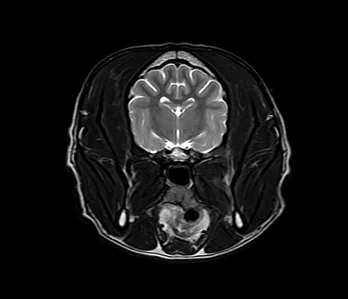

• MRI

영상의학과는 X-ray, 초음파, CT, MRI 등 다양한 첨단 장비를 활용하여 동물의 내부 상태를 영상으로 표현하고, 이를 기반으로 정확한 진단과 치료 방향을 제시하는 역할을 합니다.

• MRI 케이스 수 : 9천건 이상